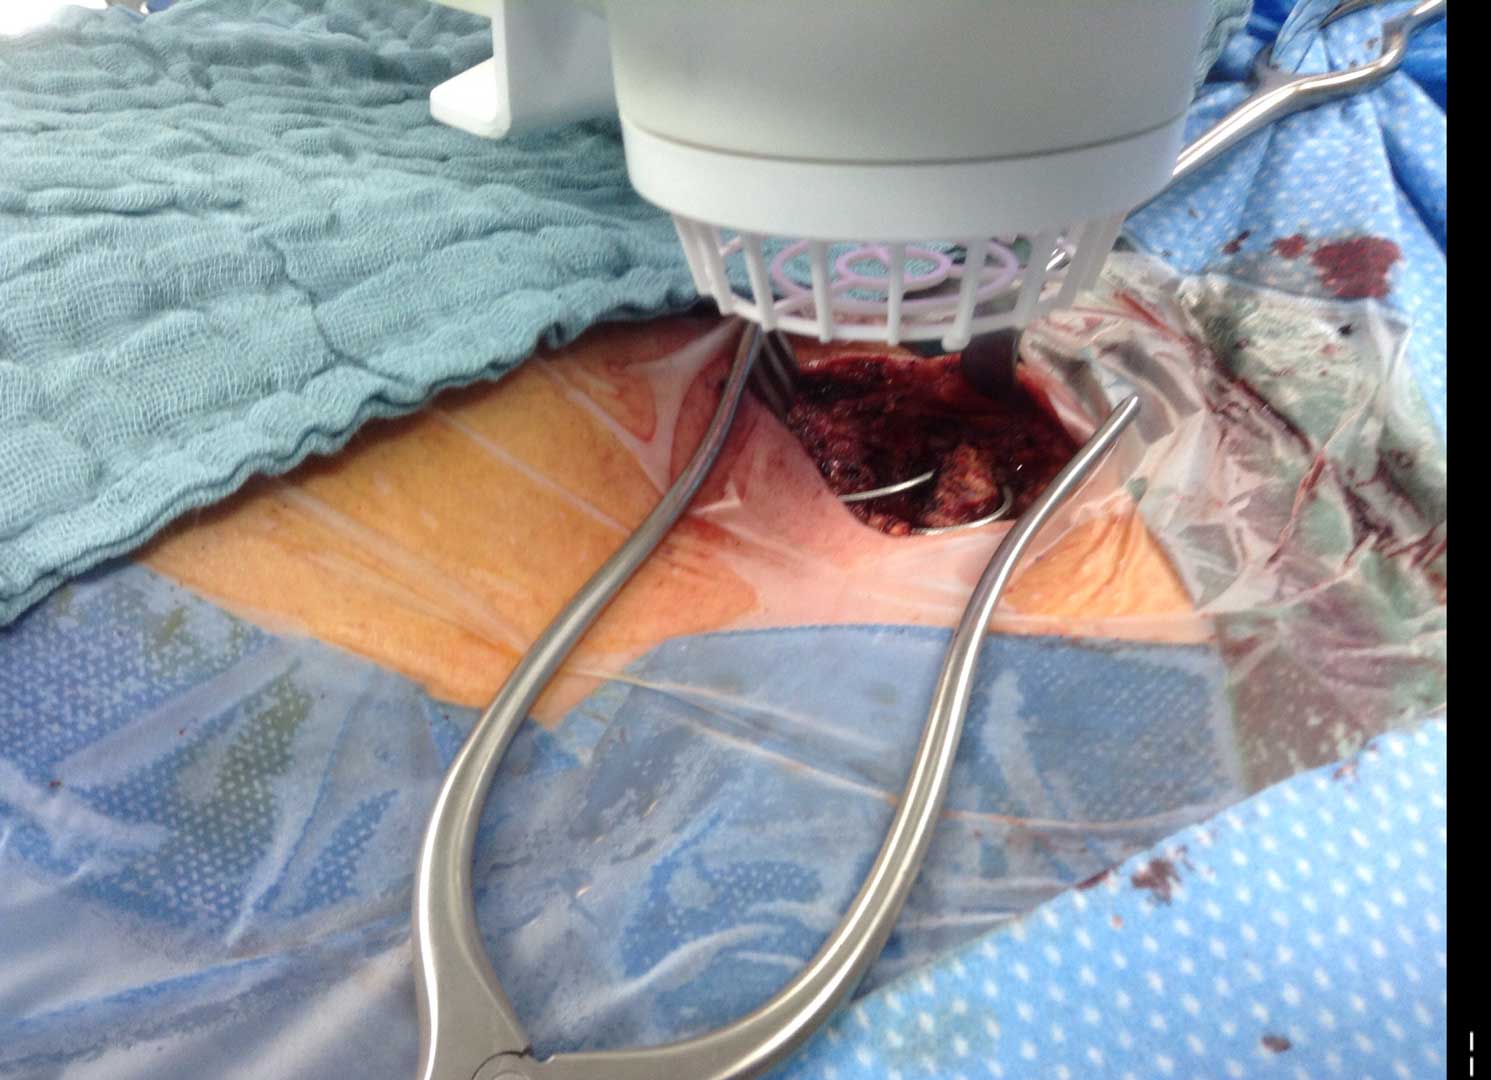

Deep Sternal Wound Infections

Deep Sternal Wound Infections (DSWIs) are infected wounds derived from complications of cardiac surgery. These are typically treated with antibiotic therapy but remain a severe problem in cardiothoracic surgery with typically a high mortality rate.

Due to exposure of the internal chest cavity that significantly increases the infection rate, it is imperative to heal these patients as quickly as possible by least invasive means necessary. As expected, antibiotics are used but in the presence of multi-resistant bacteria, this may play little to no effect.

The SteriPlas has shown to successfully treat these patients by eliminating the infection present.

This offers a new treatment approach and is a tissue saving approach and prevents the need for expensive and complex omentum majus or muscle flap plastic surgery.

Average wound closure time = 16 days of treatment.